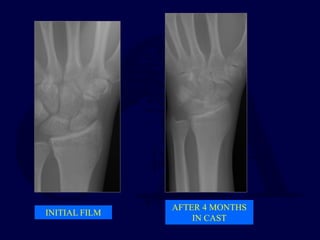

INITIAL FILM

AFTER 4 MONTHS

IN CAST